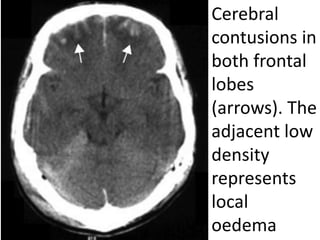

Cerebral

contusions in

both frontal

lobes

(arrows). The

adjacent low

density

represents

local

oedema

Cerebral contusion

Characteristics

● Commonest form of traumatic intra-axial injury.

● Contusions occur at the inferior and polar surfaces

of the frontal and

temporal lobes.

● Injuries may be coup or contra-coup.

● Cerebral contusions are also produced secondary

to depressed skull fractures and are associated with

other intracranial injuries.

Radiological features

● Non-contrast computed tomography (CT)

useful in the early posttraumatic period.

● Contusions are seen as multiple focal

areas of low or mixed attenuation

intermixed with tiny areas of increased

density representing petechial

haemorrhage.

● Magnetic resonance imaging (MRI) is the

best modality for demonstration of

oedema and contusion distribution.